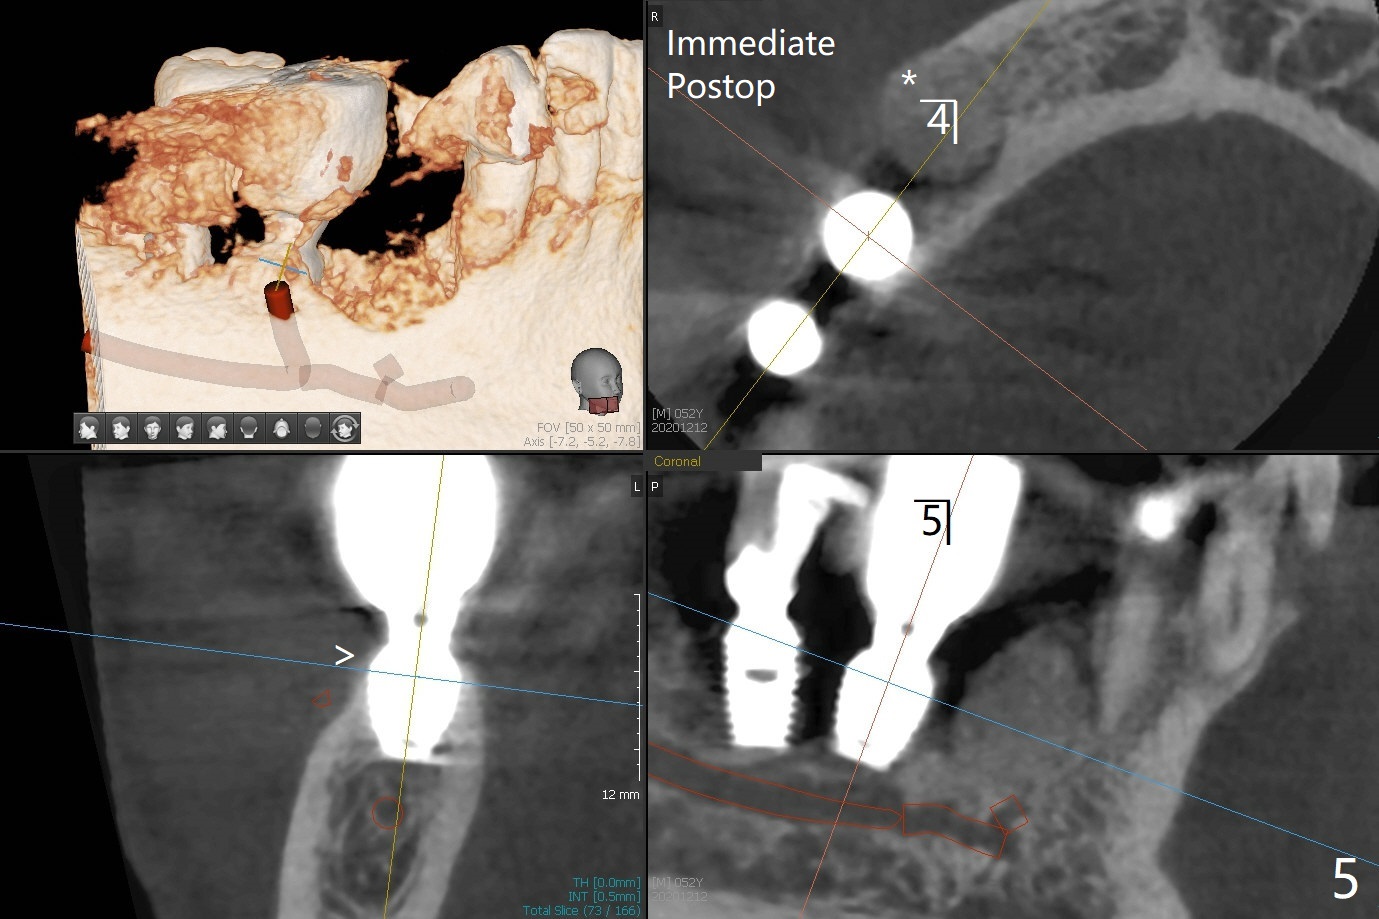

52岁男右下4植体脱落三天回到诊所(图一),植牙创尚未闭锁,顺着开口去除肉芽组织,冲洗,充填皮质骨骨粉(图二,三),颊侧骨板外形恢复(图四,五:*)。重新植入UF植体(5)颊侧还有薄颊侧骨板(图五:>),而6植体周围骨质吸收(图六),植骨好像有希望,植体还在牙槽骨范围,也有利于5植体生存。术后12天伤口愈合(图七)。尽管使用水枪,仍有6植体周围炎,需要治疗(图八)。由于右侧手术,病人不得不用左侧咀嚼,他认为左下4松动,无法挽救。术后3.5个月牙槽嵴和角化龈缩小(图九),需要切开使用导板。术后3.5个月骨粉高度明显下降(图十)。只能植入4x8.5毫米植体(图十一)。